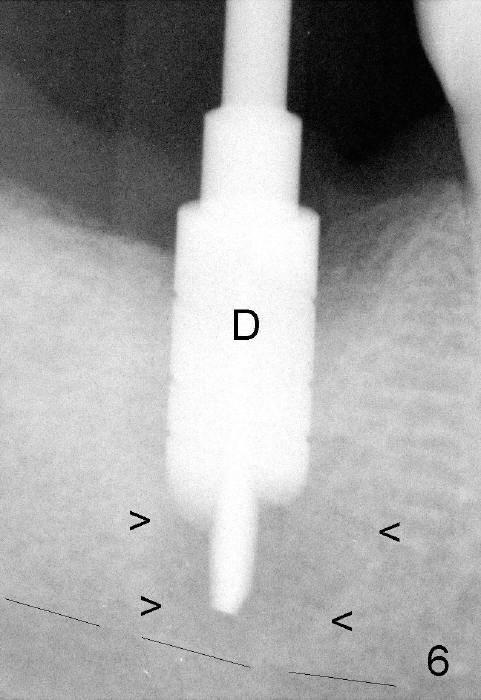

It is advantageous to place implant immediately or shortly (4-8 weeks) after extraction.  But most teeth to be extracted are potentially infected, such as in the case of Ms. Pei (Fig.1).  Periapical radiolucency (PARL) is not obvious prior to extraction. Six weeks post-extraction, osteotomy is finished with bone expansion and drilling (Fig.2 D, 5x14mm).  Tatum tapered implant is placed (Fig.3 I: 6x14). So far PARL is minimal if any (Fig.2,3 <).  Pain develops approximately 20 days post-implantation with expanding PARL (Fig.4 <).  Antibiotic treatment does not resolve the infection.  The implant has to be removed.  Infected granulation tissue is thoroughly removed from the apical portion of  the socket (Fig.5 <) with a curette (C).  Scaling and root planing is done for 4 quadrants.  A month later, potentially infected hard tissue is removed by reamers (Fig.6 D, 5 mm).  Bicon implant is buried inside the bone and separated from the oral cavity (Fig.7 I, 5x8).  At that time, there is a gap next to the implant (>).  Five months later, the gap disappears, suggesting implant osteointegration (Fig.8).  Extraoral cementation is done between abutment (A) and crown (C).  The abutment/crown unit is tapped into the implant with 2 visible threads (<).  The latter indicates that the abutment is completely seated.  Dashed lines in Fig.5-7 denote the upper border of the inferior alveolar canal.  PAs are taken 6 months (Fig.9) and 1 year 7 months (Fig.10) post cementation.  In all, it is a hassle to do re-implantation.  Efforts should be exerted to prevent post-implant infection.